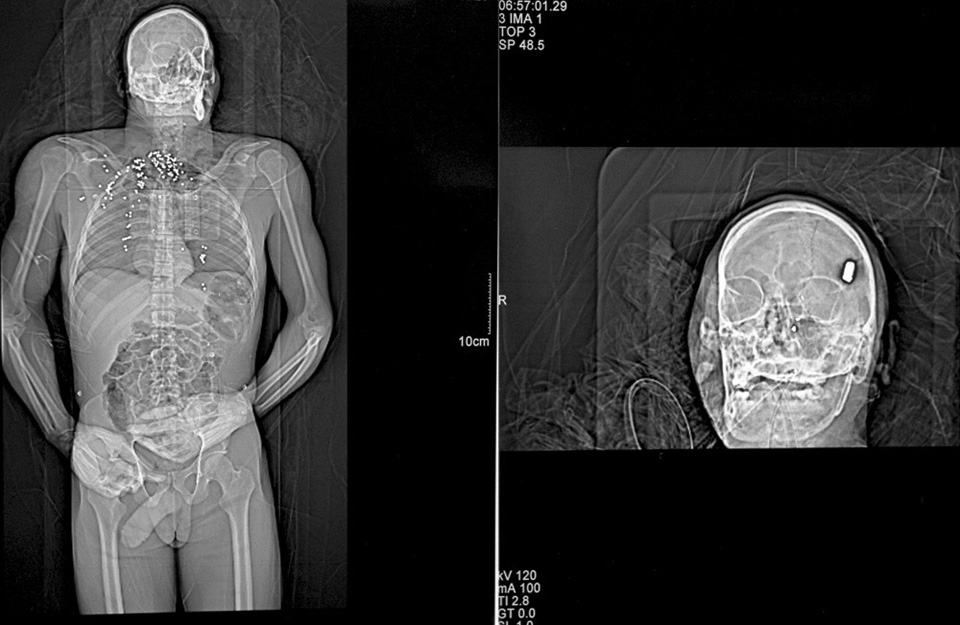

X-ray of a gunshot victim: shotgun to the chest, bullet to the head. Detroit, Michigan.